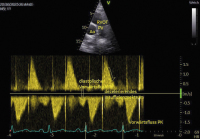

Abbildung 3: Gleicher Patient wie in Abb. 1+2; parasternale kurze Achse mit CW-Doppler über der PK. Die schwere PI erkennt man am steil dezelerierenden Insuffizienzspektrum (schräger Pfeil nach unten), sodass der Rückfluss bereits in der Mitte der Diastole aufhört. Der spätdiastolische Vorwärtsfluss nach der P-Welle (Pfeil nach unten) zeigt den Druckausgleich zwischen Pulmonalis und Ventrikel bereits in der späten Systole an.